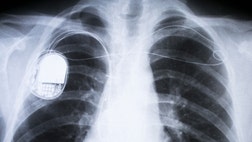

St. Jude Medical Inc. has received European approval to market the first pacemaker that does not require implanted wires to attach to the heart.

Although there are no known instances of someone hacking a pacemaker or similar device to harm another person in real life, the danger is real. That's why researchers at Rice University...